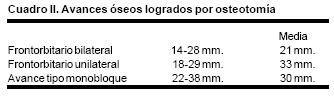

En todos los pacientes se logró el avance planificado de los segmentos óseos, al corregir la deformidad del hueso frontal, el exorbitismo y en la retrusión del tercio medio en los casos con avance en monobloque. Los avances mayores se obtuvieron en el hueso frontal y variaron entre 16 y 30 mm., mientras que los menores fueron los del hueso maxilar que fluctuaron entre 9 y 16 mm. (Cuadro I). Radiológicamente los controles postoperatorios tempranos mostraron inicialmente áreas de hipodensidad ósea, que al final del periodo de consolidación cambiaron a áreas de densidad ósea radiológica normal, lo que significa neoformación de hueso. Las áreas de hueso neoformadas que consolidaron en forma más rápida, son las ubicadas en las líneas de osteotomía de la unión pterigomaxilar, pared lateral de la órbita y unión frontoorbitaria. Las áreas que más tardaron en consolidar incluye la porción lateral y superior del hueso frontal.

También los controles radiológicos durante el proceso de distracción mostraron que no se produjo la creación de espacios muertos intracraneanos durante los avances. En todos los pacientes con sinostosis bicoronal el avance frontoorbitario produjo excelentes resultados estéticos dando una nueva forma a la región frontal y proyectando mejor el reborde supraorbitario. En los niños con enfermedad de Crouzon y síndrome de Apert, se corrigió en forma muy satisfactoria el exorbitismo al resolver las graves exposiciones corneales (Figuras 5 A, B, C, D, E, F, G, H), en los que se utilizó el avance simultáneo del tercio medio, este cambio óseo corrigió muy satisfactoriamente la retrusión del mismo, ampliando la vía aérea y resolviendo en muchos casos grandes problemas ventilatorios durante el sueño (Figuras 6 A, B, C, D, E, F). Los pacientes con plagiocefalia corrigieron significativamente la deformidad frontoorbitaria y los tejidos blandos suprayacentes se adaptaron a la nueva estructura ósea. La clásica órbita de arlequín de estos niños producida por la sinostosis del frontal con el esfenoides, inmediatamente se ve corregida en su forma y su configuración se hace muy similar con la órbita contralateral (Figura 7)(Fig. 7a, 7b, 7c, 7d, 7e, 7f, 7g) (Cuadro II).